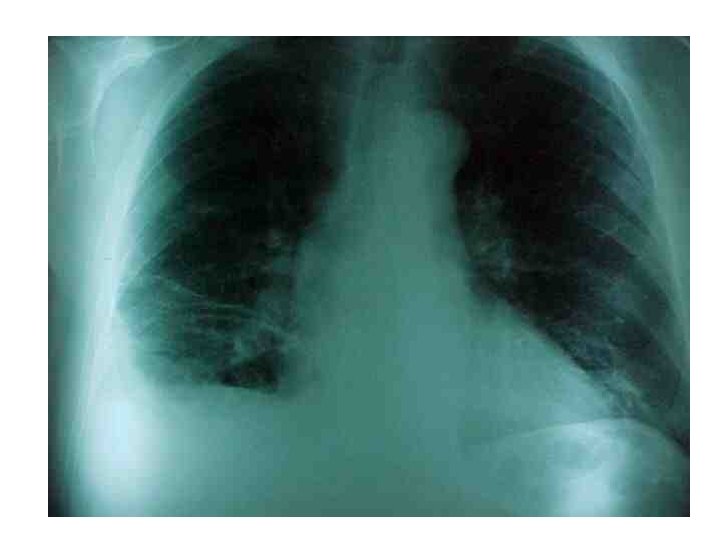

DIAGNOSTICO �EXAMENES COMPLEMENTARIOS Rx Tórax ▪ ▪ ▪ Agrandamiento cardíaco 36% Elevación hemidiafragma 26% Agrandamiento arteria pulmonar 25% Atelectasias 24% Infiltrados 23% Signo de Westmark: oligohemia focal marcada con hilio pulmonar prominente